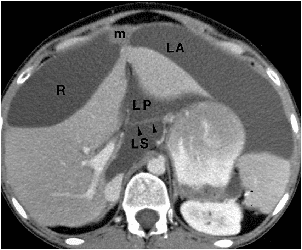

R=Right perihepatic space.

LA=left ant.perihepatic space.

LP=left post.perihepatic space.

LS=medial part of lesser sac.

arrowheads=gastroduodenal ligament.

m=metastases in falciform ligament.